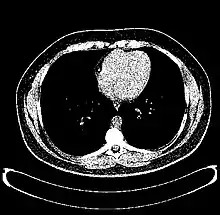

The Hounsfield scale (/ˈhaʊnzfiːld/ HOWNZ-feeld), named after Sir Godfrey Hounsfield, is a quantitative scale for describing radiodensity. It is frequently used in CT scans, where its value is also termed CT number.

HU-based differentiation of material applies to medical-grade dual-energy CT scans but not to cone beam computed tomography (CBCT) scans, as CBCT scans provide unreliable HU readings.[4]

Values reported here are approximations. Different dynamics are reported from one study to another.

Exact HU dynamics can vary from one CT acquisition to another due to CT acquisition and reconstruction parameters (kV, filters, reconstruction algorithms, etc.). The use of contrast agents modifies HU as well in some body parts (mainly blood).

A practical application of this is in evaluation of tumors, where, for example, an adrenal tumor with a radiodensity of less than 10 HU is rather fatty in composition and almost certainly a benign adrenal adenoma.[28]